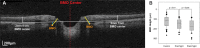

Prolonged microgravity exposure during long-duration spaceflight (LDSF) produces unusual physiologic and pathologic neuro-ophthalmic findings in astronauts. These microgravity associated findings collectively define the "Spaceflight Associated Neuro-ocular Syndrome" (SANS). We compare and contrast prior published work on SANS by the National Aeronautics and Space Administration's (NASA) Space Medicine Operations Division with retrospective and prospective studies from other research groups. In this manuscript, we update and review the clinical manifestations of SANS including: unilateral and bilateral optic disc edema, globe flattening, choroidal and retinal folds, hyperopic refractive error shifts, and focal areas of ischemic retina (i.e., cotton wool spots). We also discuss the knowledge gaps for in-flight and terrestrial human research including potential countermeasures for future study. We recommend that NASA and its research partners continue to study SANS in preparation for future longer duration manned space missions.